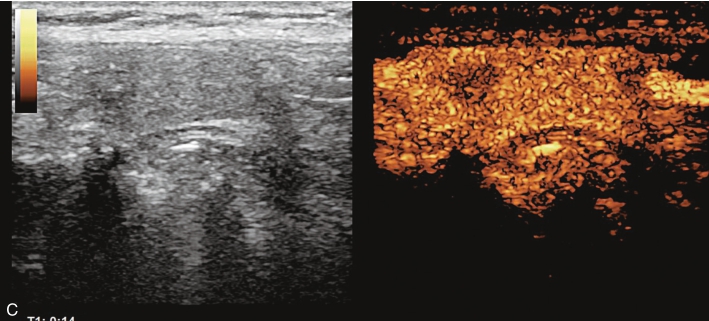

注射造影剂后,10s病灶早于周围甲状腺组织开始增强,呈不均匀高增强,13s达峰值,19s开始减退,至增强晚期病灶减退呈不均匀稍低增强。见图1-9-2、ER1-9-1。

图1-9-2 甲状腺髓样癌造影图像

A.造影后10s;B.造影后13s;C.造影后19s;D.增强晚期